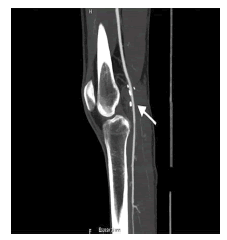

Con la confirmación diagnóstica de enfermedad quística de la adventicia, se decidió intervenirlo quirúrgicamente. Se utilizó un abordaje posterior de la fosa poplítea (figura 4) que expuso la lesión quística dependiente de la pared arterial. Se resecó el segmento afectado (figura 5) y se reparó el defecto con intercalación de injerto autólogo de vena safena (figura 6). El paciente evolucionó favorablemente, sin complicaciones inmediatas. Acudió a control meses después de la cirugía, sin síntomas. Se practicó una angiografía por tomografía computadorizada (TC) de control, que demostró un adecuado flujo sanguíneo en el injerto (figura 7).